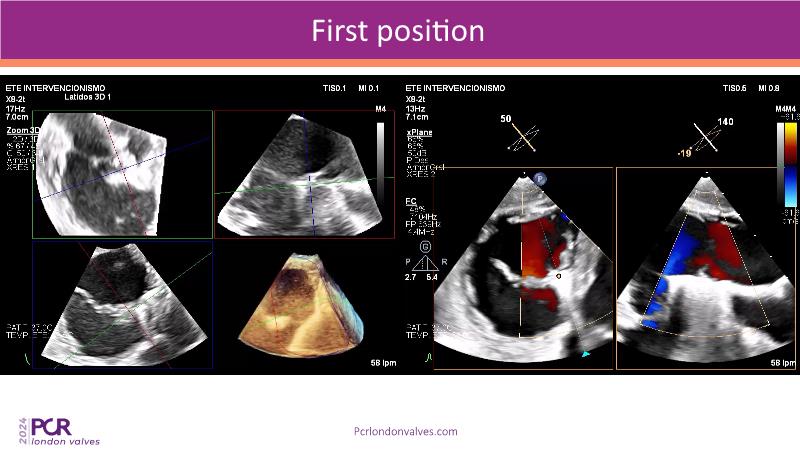

This session examines two compelling cases: a 78-year-old woman with paroxysmal atrial fibrillation, chest trauma, an osteoporotic sternum fracture, and NYHA II exertional dyspnoea, and an 82-year-old man with chronic three-vessel coronary artery disease, bradycardic AF, peripheral arterial disease, spinal stenosis, and chronic kidney disease. Through their study, discover the intricate anatomy of atrioventricular valves, the therapeutic challenges they pose, and the growing significance of transcatheter edge-to-edge repair (TEER) therapies. The discussion also highlights the value of multidisciplinary strategies in managing complex valve diseases effectively.